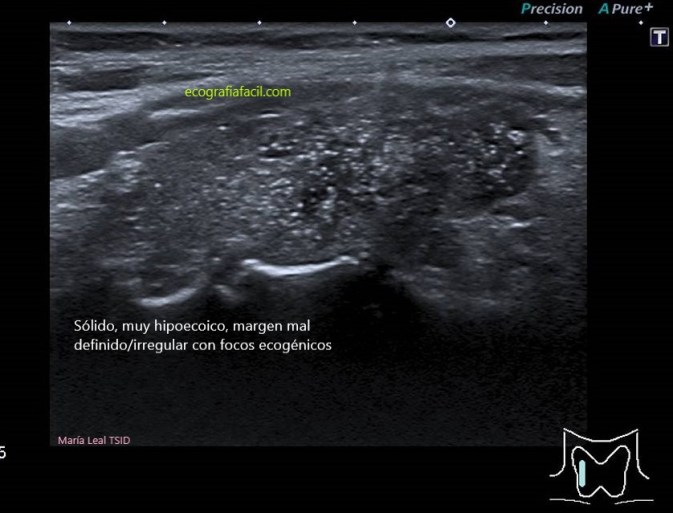

TI-RADS 5

Alta sospecha de malignidad (mayor del 80%)

COMPOSICIÓN: Sólida                           2

ECOGENICIDAD: Muy hipoecoica          3

FORMA: Más ancho que largo               0

MARGEN: Irregular                                 2

FOCOS ECOGÉNICOS: (puntiformes)       3

10 puntos